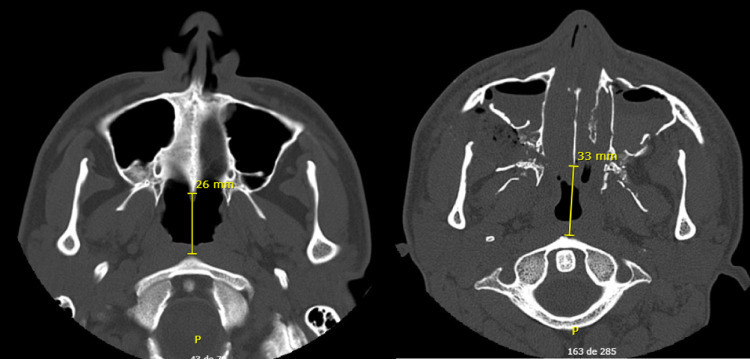

Axial images demonstrate the increase in the distance between the anterior nasal spine and the body of the axis (Fig. 27). The preop distance was of 26 mm and the postop of 33 mm.

Fig. 27.

Axial views of the CT scan demonstrating midface advancement